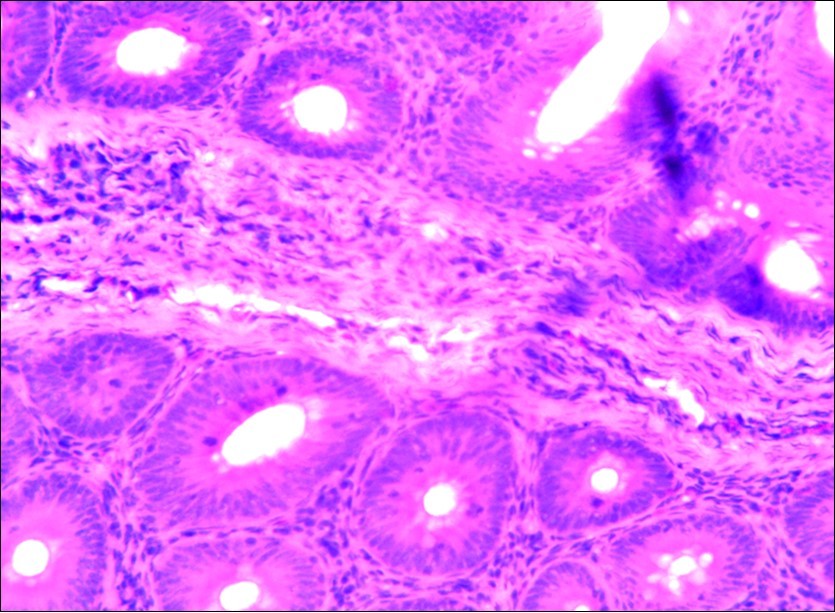

Figure 3.Photomicrograph of caecum of chick uninfected and untreated showing no observable lesion X250 (H&E).